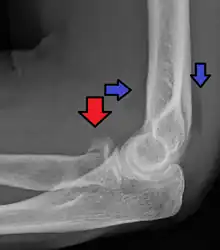

| Radial head fracture (red arrow) with posterior and anterior sail sign (blue arrows) | |

Radial head fractures are diagnosed from a clinical assessment and diagnostic imaging. Clinical assessment may include pain or tenderness at the radial head, bruising, swelling, and a limited range of motion of the injured elbow.[2] Diagnostic imaging may include ultrasound, plain radiography (x-ray imaging), Computed tomography scan (CT), and magnetic resonance imaging (MRI).[2][4] A fat pad sign may be present on diagnostic imaging and may indicate a radial head fracture.[5]